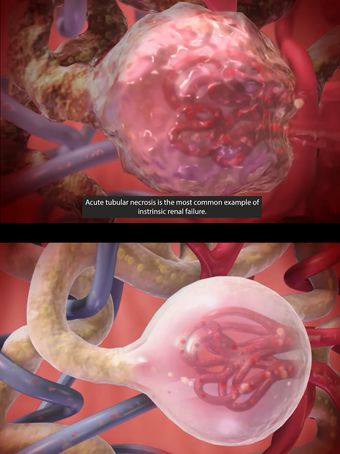

One of the most remarkable features of this application is that it enables users to compare 3D models of normal anatomy with models of common diseases and conditions. Furthermore, users can set the heart rate and visualize conduction in a dissectable, beating 3D heart while following along on an ECG. The application also presents animations that demonstrate the physiological processes of gas exchange, pulmonary ventilation, fluid balance, peristalsis, and more. Interactive lessons walk users through the progression of atherosclerosis, kidney stones, lung cancer, and other common conditions, and quizzes test users' knowledge of various physiological processes and pathologies.